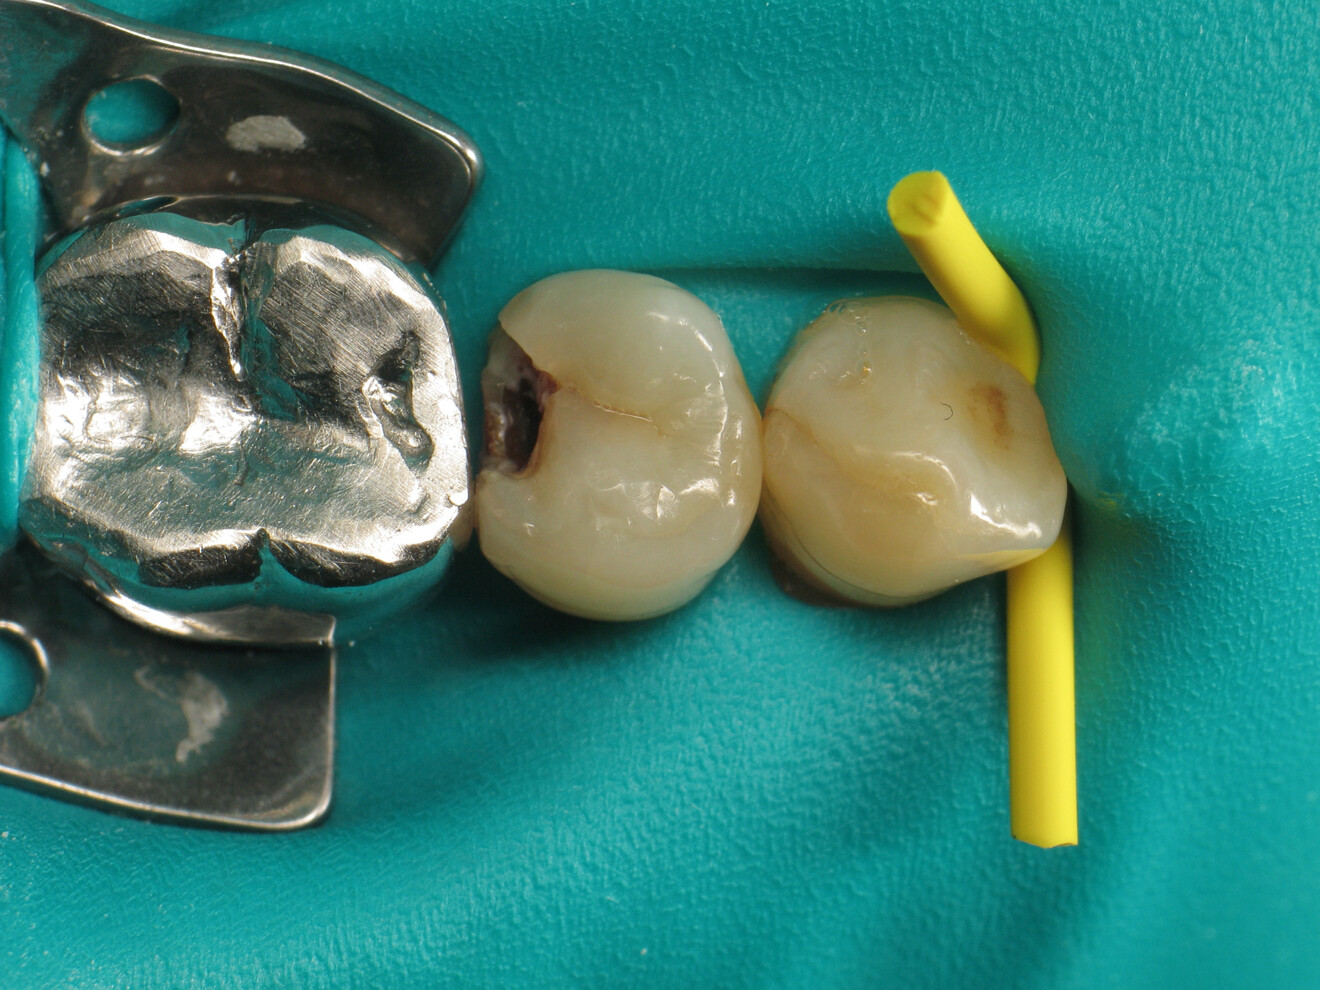

Fig. 3: Cavity after excavation.

The clinical case described in this article concerns a Class II cavity in a premolar (tooth #45) restored using a thermo-viscous composite (Fig. 1). The tooth was isolated with a dental dam (Fig. 2). The cavity was then cleaned (Fig. 3). In order to obtain an anatomically correct distal wall, a matrix, a wedge and a ring were placed (Fig. 4). The tooth enamel was then etched for 30 seconds and the dentine for 15 seconds (DeTrey Conditioner 36, Dentsply Sirona; Fig. 5) and then rinsed and dried thoroughly (Fig. 6). Owing to the thinness of the remaining dentine, pulp protection (Telio Desensitizer, Ivoclar) was also applied (Fig. 7).